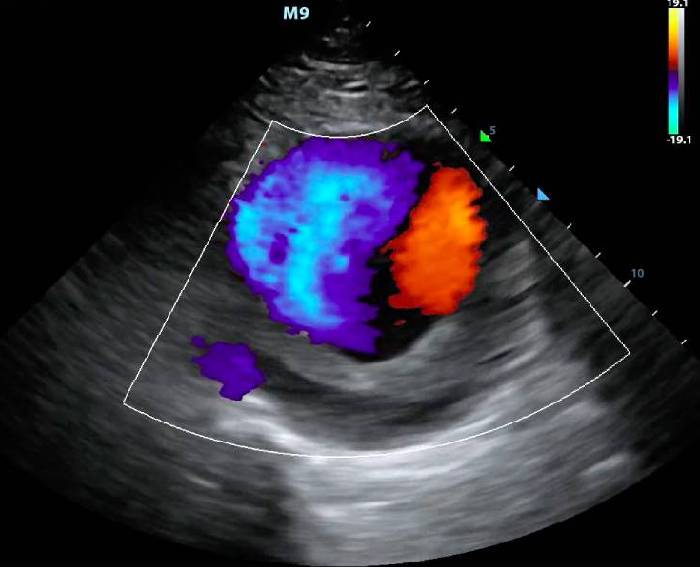

Color Ultrasound

Echocardiography